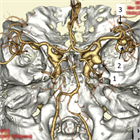

1. 未破裂脳動脈瘤の診断は、カテーテル法によるDSA:digital subtraction angiographyおよびその3次元血管撮影像がゴールドスタンダードである。3D-CTA:3次元ヘリカルコンピュータートモグラフィー、MRA: magnetic resonance angiographyなどは低侵襲な代替え診断法として未破裂脳動脈瘤の診断および治療に用いることが妥当である(推奨度1、J)